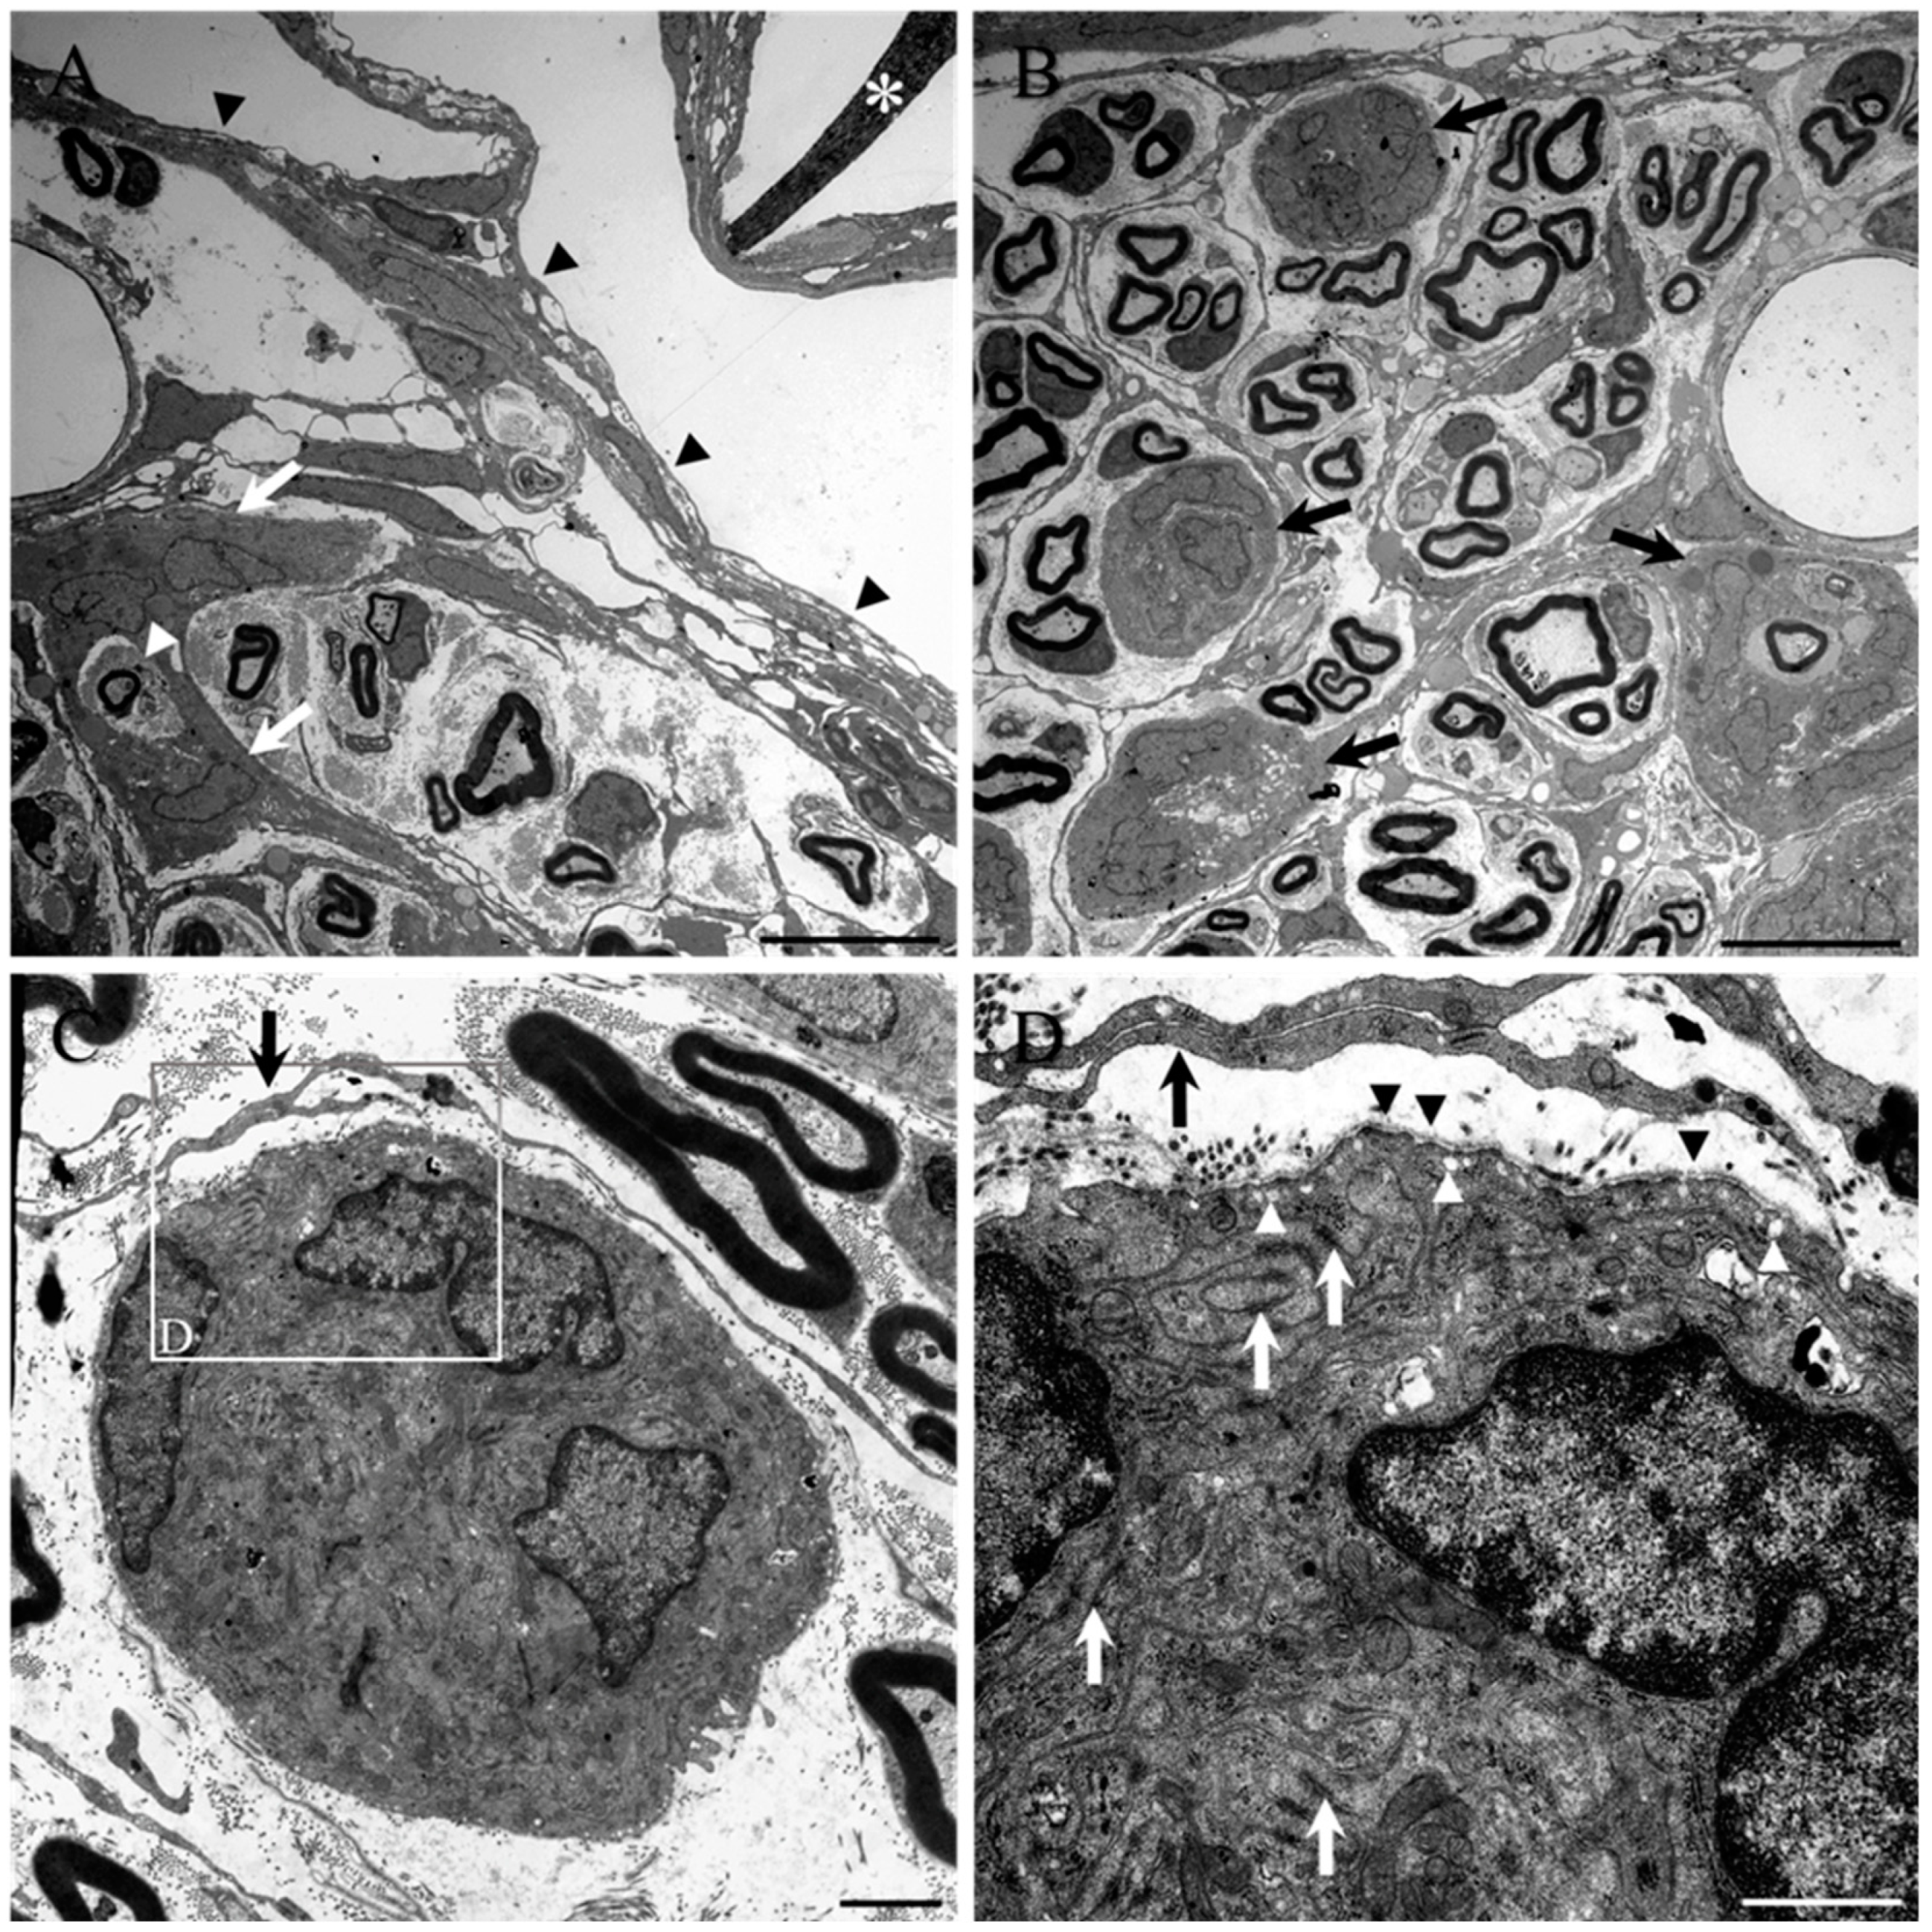

- Altinova, H.; Hammes, S.; Palm, M.; Achenbach, P.; Gerardo-Nava, J.; Deumens, R.; Fuhrmann, T.; van Neerven, S.G.A.; Hermans, E.; Weis, J.; et al. Dense fibroadhesive scarring and poor blood vessel-maturation hamper the integration of implanted collagen scaffolds in an experimental model of spinal cord injury. Biomed. Mater. 2020, 15, 015012. [Google Scholar] [CrossRef] [PubMed]

- Altinova, H.; Hammes, S.; Palm, M.; Gerardo-Nava, J.; Achenbach, P.; Deumens, R.; Hermans, E.; Fuhrmann, T.; Boecker, A.; van Neerven, S.G.A.; et al. Fibroadhesive scarring of grafted collagen scaffolds interferes with implant-host neural tissue integration and bridging in experimental spinal cord injury. Regen. Biomater. 2019, 6, 75–87. [Google Scholar] [CrossRef] [PubMed] [Green Version]